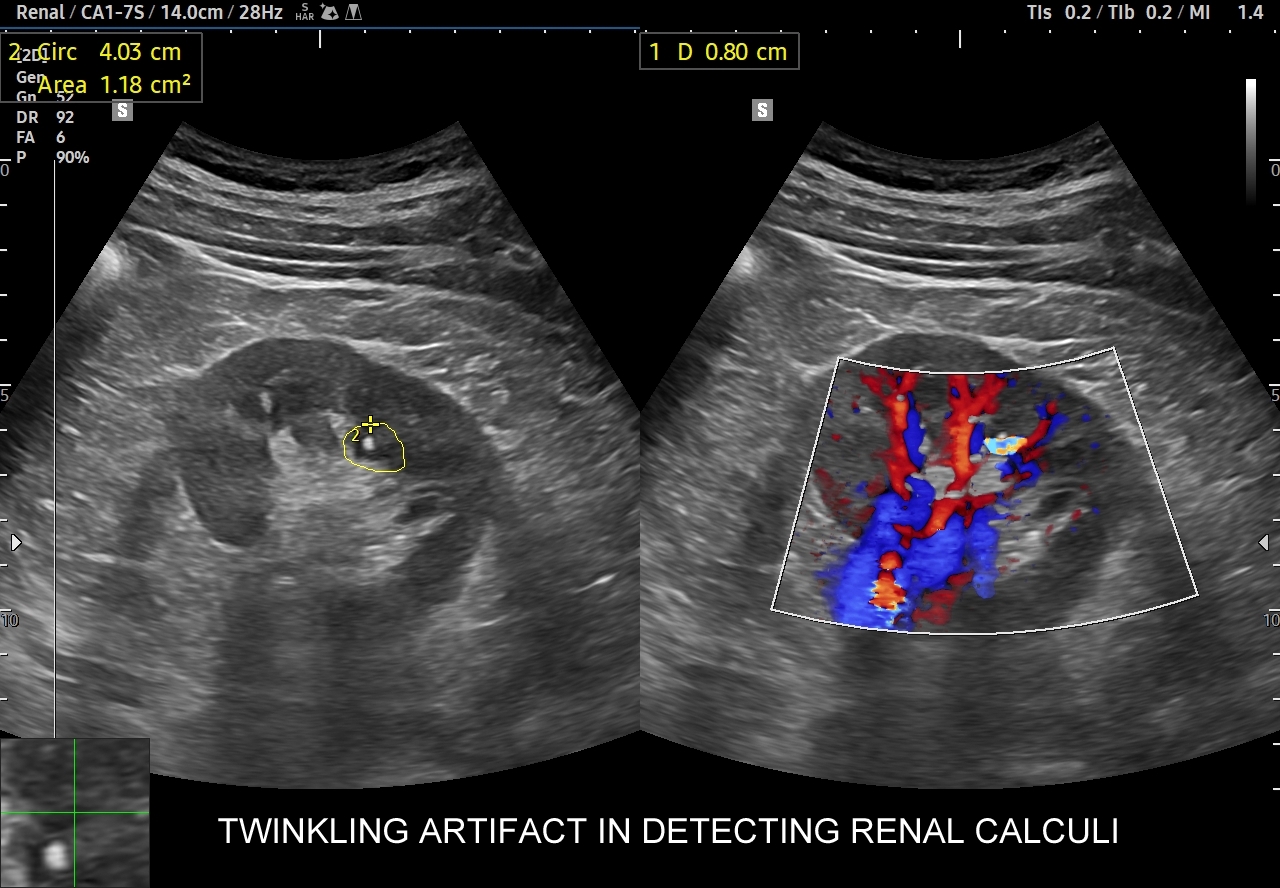

Badania obrazowe służące wykrywaniu kamicy moczowej to badanie RTG, CT, lecz przede wszystkim badanie USG. W badaniu USG nerek w prezentacji B kamica nerkowa widoczna jest w sytuacji, gdy złogi są odpowiednio uwapnione, odpowiednio duże oraz nie zlewają się z zatoką tłuszczową miedniczki nerki. Zasadniczo złogi w trybie B będą widoczne wyraźniej, gdy położone są w miąższu nerki; z kolei w miedniczce nerkowej, gdy są na tyle duże, że dają artefakt cienia. Czasem w celu uwidocznienia złogu przydatne jest wyłączenie wspomagania typu x-beam.

Ważnym trybem pomocniczym jest color-Doppler, w którym to trybie uzyskuje się tzw. artefakt migotania, często nawet na bardzo drobnych złogach niewidocznych w trybie B. Uzyskanie efektu migotania jest niestety zależne o jakości aparatury USG, a także od ustawień Dopplera i software’u.

W modalnościach dopplerowskich oprócz prezentacji color-Doppler artefakt migotania pojawia się także w trybie Dopplera spektralnego. Otóż po umieszczeniu bramki dopplerowskiej na złogu uzyskuje się charakterystyczny, dźwiękowy objaw trzeszczenia, a na obrazie wykresu wypełnienie sygnałem całego spektrum częstotliwości.